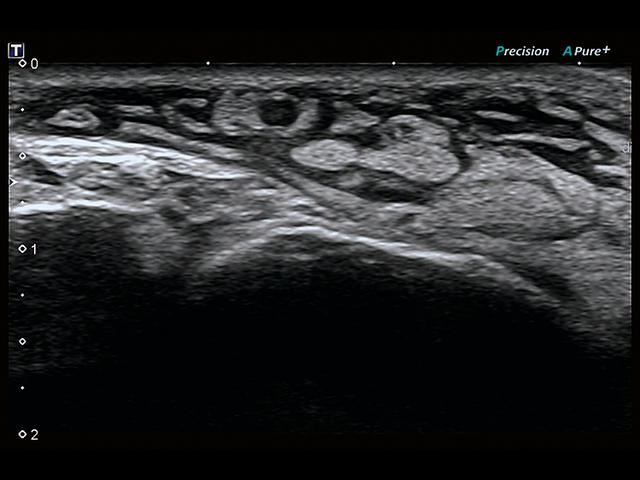

Aplio 500 – ультразвуковой сканер премиум класса, сочетающий в себе быстродействие диагностики и отличное качество визуализации. Более 30 датчиков на выбор, в т.ч. матричные, монокристаллические, 4D, эндоскопические для любых типов исследований. Ультразвуковой сканер позволяет изучать анатомические структуры в высоком разрешении.

Обновленная версия легендарного УЗ-сканера. Стационарный аппарат экспертного класса Aplio 500 Toshiba NEW, визуализирует анатомические структуры в высоком разрешении. Модель позволяет выявить микрокальцификаты, новообразования, нарушения в работе сердца, сосудов и мышц. Присутствует функция виртуальной эндоскопии, 4D-сканирования, эластометрии тканей, УЗИ с контрастированием. За повышение качества изображения отвечают технологии ApliPure и Superb Microvascular Imaging. Первая задействует возможности пространственного и частотного кодирования, формирует цельный визуальный ряд с сохранением клинических маркеров. Вторая улучшает отображение микрососудистого русла, используя доплеровский эффект. Модель оснащена 21-дюймовым монитором, имеет 4 активных порта. Возможно подключение педиатрических, интраоперационных, лапароскопических и чреспищеводных датчиков.

• D-THI.Режим дифференцированной тканевой гармоники, повышающий качество визуализации глубоко расположенных тканей. Получаемое изображение отличается высокой четкостью, не содержит дефектов в виде «заснеженных» и размытых участков.

• SMI. Опция, упрощающая визуализацию микроциркуляторного русла. С ее помощью обследуются сосуды с низкой интенсивностью кровотока, изучаются наиболее тонкие структуры. SMI упрощает диагностику новообразований, минимизирует вероятность ошибки.